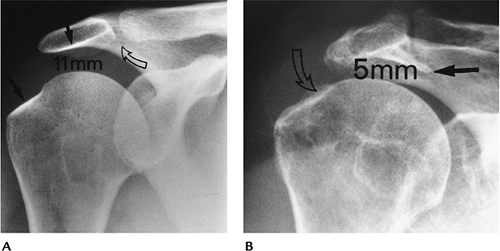

FIGURE 7-14 (A) Normal AP shoulder radiograph with 11-mm humeroacromial distance, normal greater tuberosity, and acromion (black arrows), and no abnormalities in the AC joint (curved open arrow). (B)

AP radiograph in a patient with a chronic rotator cuff tear. The humeroacromial space is 5 mm (normal >7 mm). There is a prominent subacromial osteophyte (black arrow) causing impingement and bony irregularity (open curved arrow) in the greater tuberosity. |